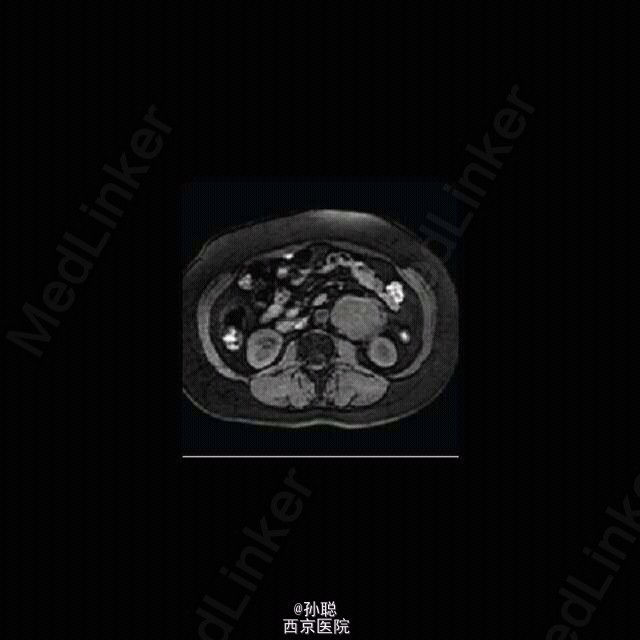

一名 40 岁女性因无症状左肾肿块入住外科病房。病灶因妇科 B 超体检偶然发现。既往无相关病史。患者无腹部不适、腰背痛、消瘦、汗出、疲劳或发热。体格检查无殊。浅表淋巴结和脏器未及肿大。血常规和生化等实验室检查均正常。 进一步查腹部 CT 显示左肾旁一 7.6×5.3×12cm 肿块,血供丰富、边界清,未侵犯周围组织。腹腔其余部位、纵膈和肺部未见肿瘤。 行剖腹探查术。术中将病灶完整地自左侧腹部取出。病理诊断明确 Castleman’s 病,透明 / 血管变异。术后恢复顺利,患者于术后第 5 日出院。术后一年患者健康状况良好。CT 随诊无复发或其它病变。